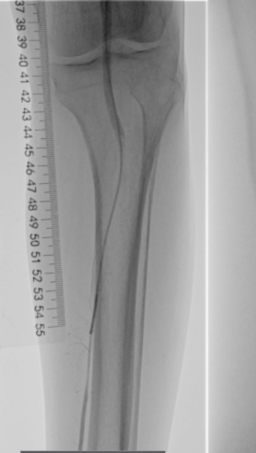

术前下肢动脉CTA提示:左下肢股、腘动脉长段闭塞,膝下动脉主干未见显影,可见少量侧支血流。

血管外科姜坤主任团队仔细分析患者病情,该患者在动脉硬化闭塞基础上继发血栓形成,且血栓负荷量大,身体状况差,行麻醉及开放手术取栓的风险大,遂制定了微创腔内的手术方案,采用动脉机械血栓清除+血管成形术。

术中选用Rotarex导管行血栓清除,对管腔内残留的血栓放置溶栓导管,最后采用球囊扩张狭窄病变,管腔获得满意。

治疗后者患者肢体、疼痛缓解,无远端血管栓塞,无缺血再灌注损伤,3日后顺利出院。